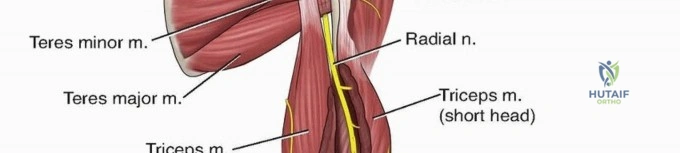

The radial nerve is the most critical anatomical structure at risk during both the initial injury and subsequent surgical approaches to the humerus. The nerve, accompanied by the profunda brachii artery, exits the axilla and passes through the triangular interval. This interval is bordered superiorly by the teres major, medially by the long head of the triceps, and laterally by the humeral shaft.

From the triangular interval, the radial nerve transverses from medial to lateral along the posterior aspect of the humeral shaft within the spiral groove. It pierces the lateral intermuscular septum approximately 10 to 12 centimeters proximal to the lateral epicondyle to enter the anterior compartment of the arm. Distally, the nerve travels in the anatomic interval between the brachialis muscle medially and the brachioradialis muscle laterally. This specific interval is the foundation of the distal anterolateral approach to the humerus.